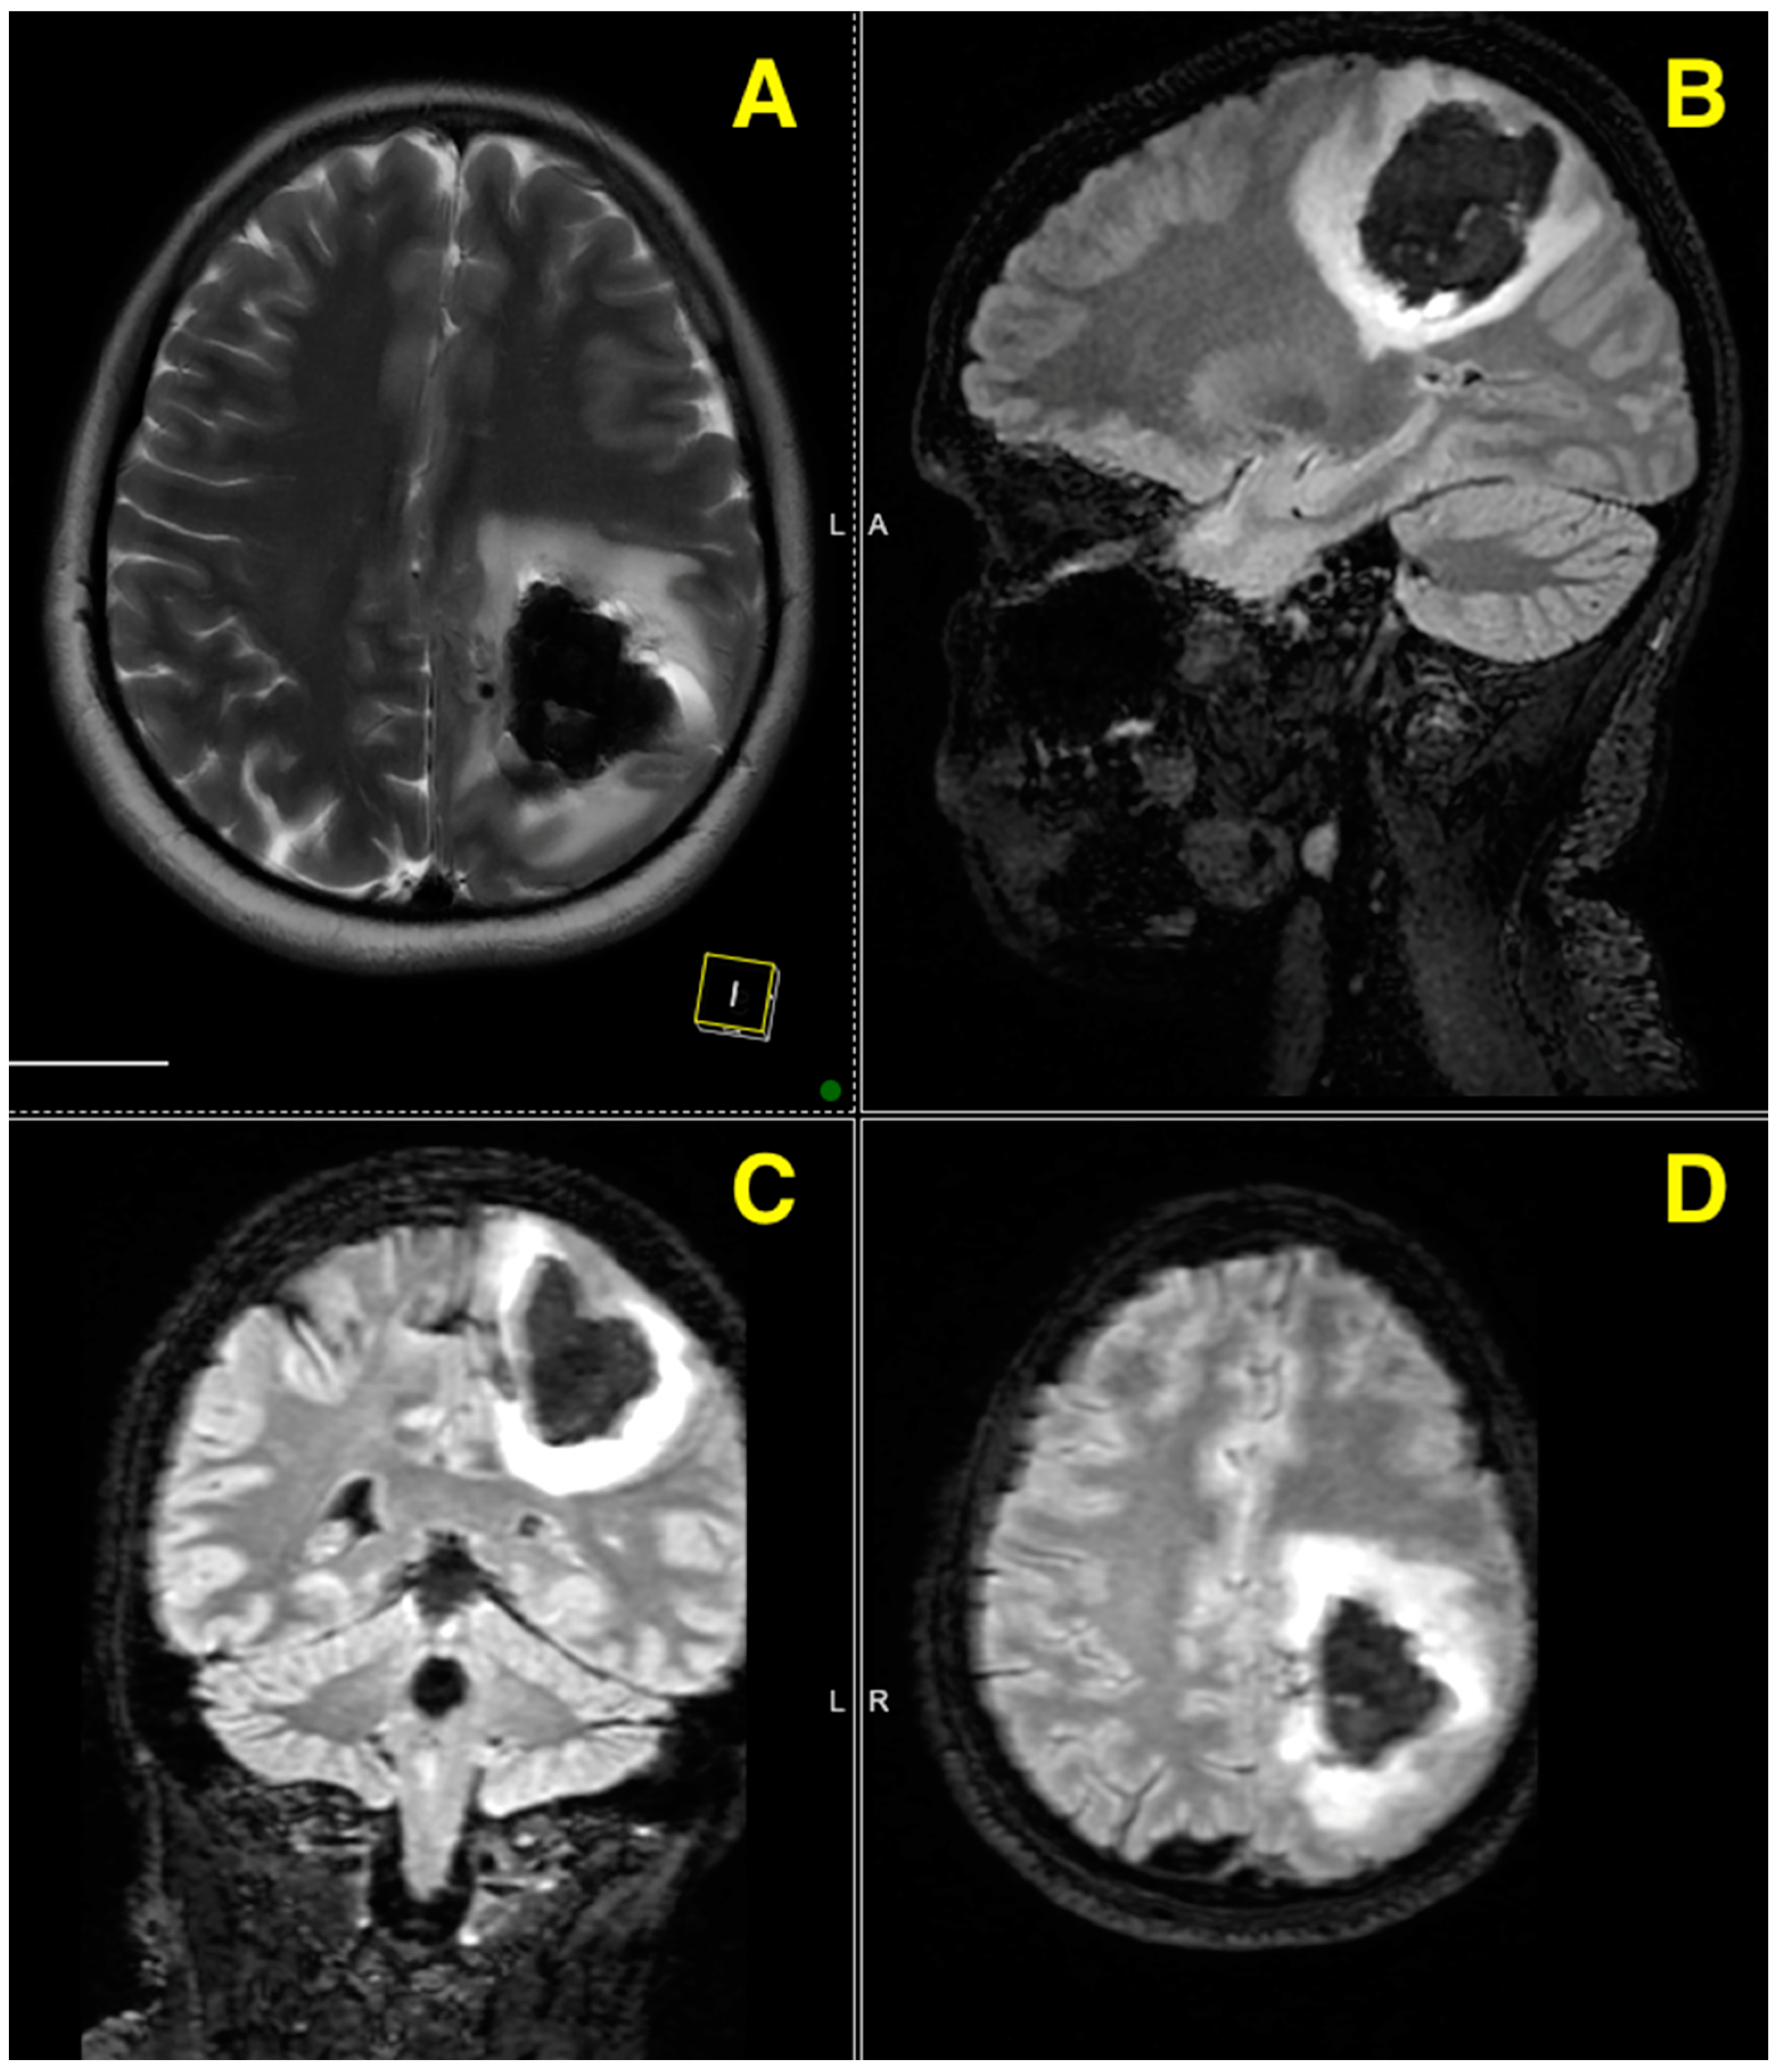

Challenging Management of a Rare Complex Cerebral Arteriovenous Malformation in the Corpus Callosum and Post-Central Gyrus: A Case Study of a 41-Year-Old Female

2. Case Presentation